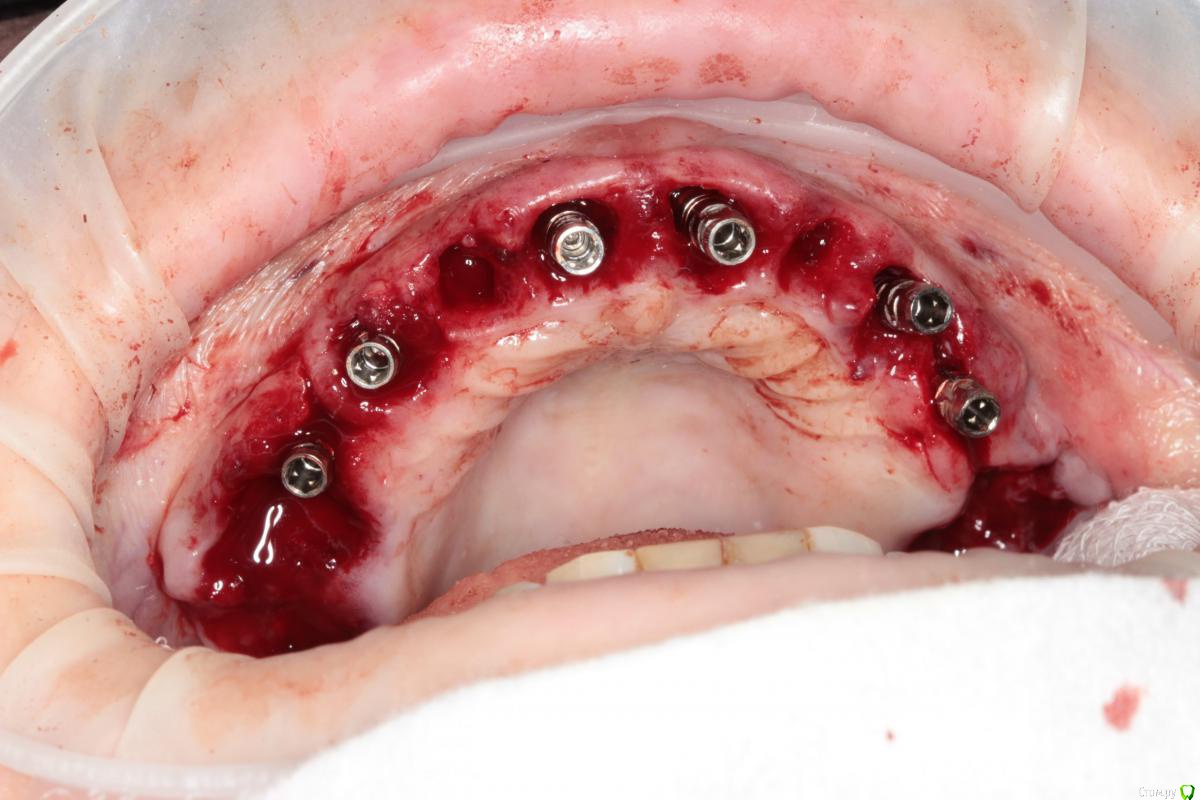

Популярный пост Abuk Опубликовано 24 ноября, 2015 Популярный пост Поделиться Опубликовано 24 ноября, 2015 Планировали 8 имплантатов.Буду рад конструктивной критике.Фото с мокап.Через 6 днейДалее хотели поставить 6 ки, она отказалась (не хотели синусы)и решили все по-другому .Через 2мес пришла с отколотыми консолями )Прошу прощения ,что ортопедию выложил не в том разделе), не хотел делить. 26 1 Ссылка на комментарий

Abuk Опубликовано 24 ноября, 2015 Автор Поделиться Опубликовано 24 ноября, 2015 (изменено) Радикально Вы. Что оставили ей после имплантации-это инд аббатменты? На них мокап одели и нагрузили сразу? У всех был торк хороший? Или это временные абб? Что за систему использовали? В планах консоль назад, правильно я понимаю?Спасибо.увидев такую работу,сам так же подумал бы). Но там подвижность 2-3 ст. ближе к 3. Мосты болтались ,2 ки в хлам. 1 ки только стабильны. Снимал мосты,проводил кюретаж. Решил дернуть.Абатманы временные, тех. сделал на них коронки. Система анкилоз. Работа,на посл. фото, постоянная . Имплы в области 4 и по одному моляру ,консоли. Мок ап был до имплантации . По нему шаблон. Стабильность 15 -20 на 23 , остальное больше 30. Изменено 24 ноября, 2015 пользователем Abuk 1 Ссылка на комментарий

Abuk Опубликовано 24 ноября, 2015 Автор Поделиться Опубликовано 24 ноября, 2015 Вы лунки тоже аугментиовали?Хирургия понравиласьДа, спасибо. Если не сложно, напишите что вам не понравилось в ортопедии.Техничка мне самому не очень , хотя многим ,включая пациента, понравилась Ссылка на комментарий